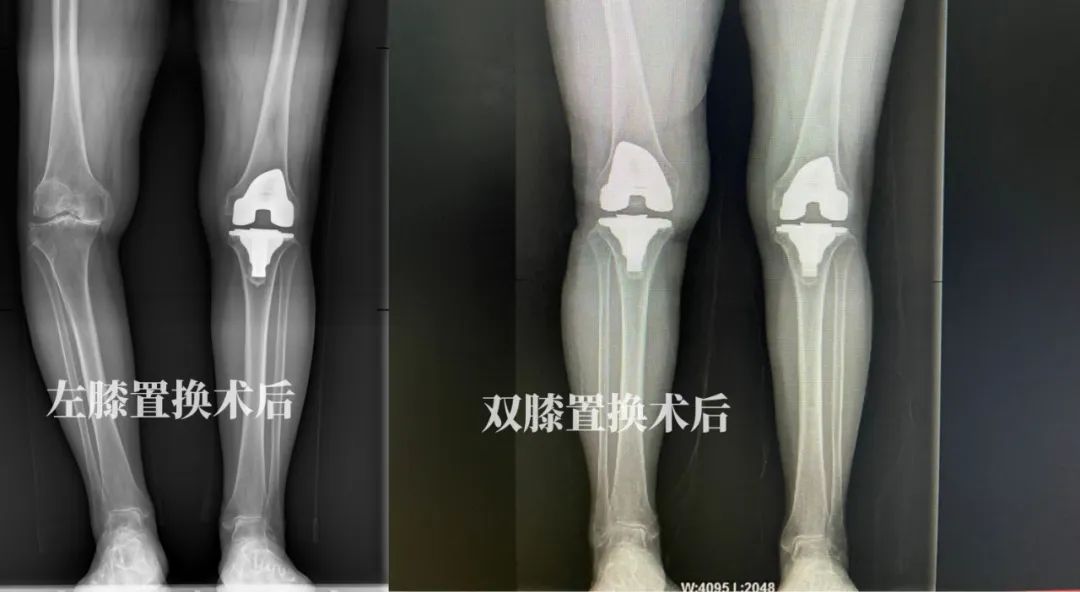

【双膝关节置换,告别多年顽疾】坐着轮椅进医院,自己走着回家

成都市龙泉驿区中医医院(成都中医药大学附属龙泉医院)骨伤科,四川省省级重点中医专科,技术力量雄厚、技术精湛,现有高、中、初级职称医护人员76名,其中医生33人,护理43人,康复治疗师3人,硕士研究生16人。现有床位200张,目前开放床位150张,分别为骨一科(创伤)50张,骨二科(脊柱)50张,骨三科(关节、运动医学)50张。开展了人工全髋、半髋、全膝关节置换术、单髁置换术、髋膝关节翻修术、脊柱前后路减压植骨内固定术、脊柱微创手术(PKP、PVP、椎间孔镜)、肩、膝关节镜、四肢骨折内固定术、四肢矫形术、皮瓣转移、断肢再植、骨与软组织肿瘤等手术治疗。